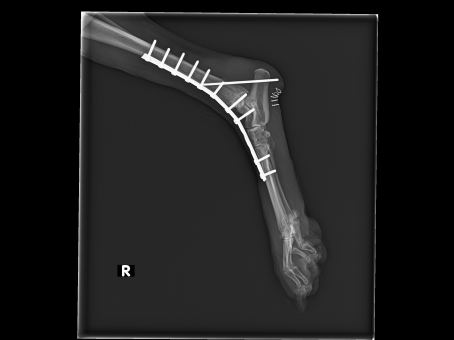

Wie gut kann ich mich daran erinnern, welchen „Kampf“ wir führen mussten, um Luna zu uns holen zu können. Ohne die Hilfe und das Engagement von Annette und Wilfried hätte Luna mit ihrem schlimm verletzten Bein sicher noch länger leiden müssen.

Als sie endlich bei uns ankam, war das Entsetzen unbeschreiblich. Es war uns sofort klar, dass wir alles unternehmen würden, um ihr Leiden zu beenden, koste es was es wolle! Es folgte eine lange Zeit mit einigen nicht einfachen und bestimmt schmerzhaften Therapien und Operationen. Aber dieses sanfte Wesen Luna ertrug wirklich alles, als ob sie verstünde, dass sie eines Tages ein ganz normales Hundeleben führen würde.

am 28.11.2014 kamst Du mit einer schweren Beinverletzung zu CIN. Es folgte eine lange Zeit mit regelmäßigen Untersuchungen und Verbandswechseln. Diese und auch mehrere noch folgende Operationen hast Du immer mit großer Geduld ertragen. In den folgenden Monaten gab es viele Höhen und Tiefen, aber Du hast immer einen Weg gefunden mit Deinem immerhin nicht unerheblichen Handicap umzugehen. Du warst ja auch bei Margit und in der Tierklinik Dr. Berger in Heede in sehr guten Händen und hast dort sehr viel Liebe und Fürsorge erfahren dürfen.